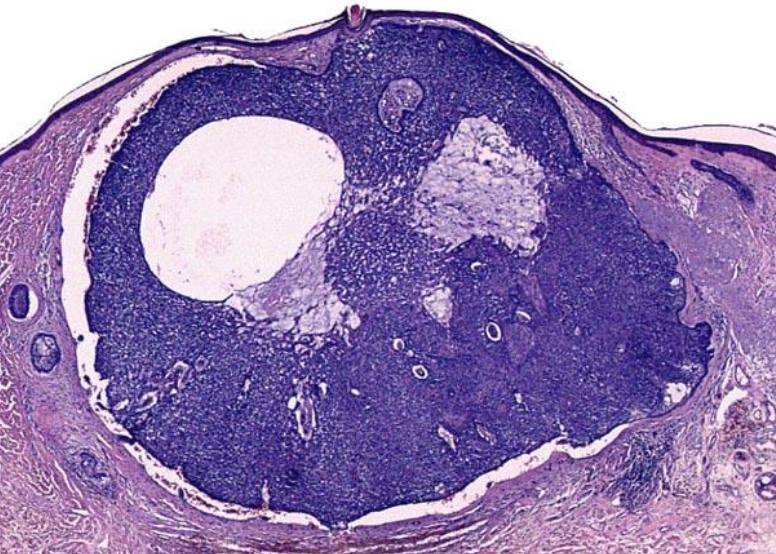

3

A

Acute Eczematous Dermatitis

Erythmetous: papulovesicular oozing and crusted